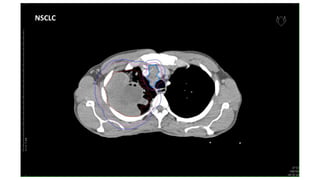

NSCLC

CT images ofCa Lungs